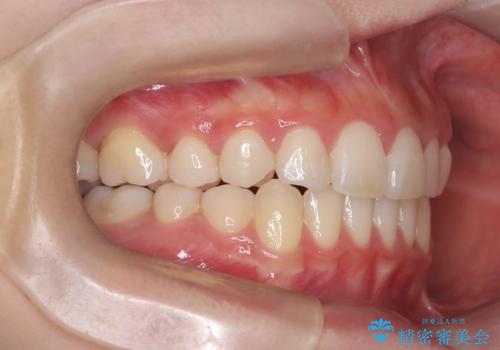

- 八重歯を主訴に来院された患者様です。

インビザラインによる矯正を希望され、今回は移動距離が少なくなるように犬歯を抜歯する治療計画としました。

抜歯矯正において、通常では4番(第一小臼歯)が抜歯の対象となることが多いのですが、今回は3番(犬歯)の歯肉退縮や装置の特性を考慮した治療計画となります。

下顎に関しては、半年ほどワイヤー矯正にてリカバリーを行なっております。